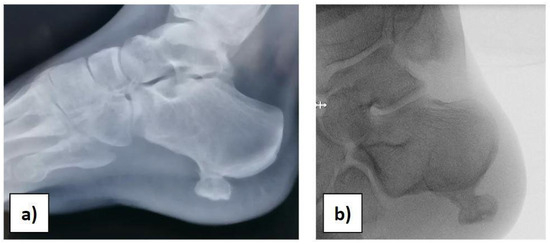

At the orthopaedic clinical examination, a stiff, immobile, and painful mass measuring approximately 2 × 1.5 cm was palpated in the heel region. The range of motion of the ankle was complete. The girl was subjected to an X-ray examination of the foot in anterior–posterior, later-lateral, and oblique projections, which revealed a 2 × 1, 5 × 1 cm pedunculated bone lesion involving the load-bearing part of the heel, arising from the posterolateral aspect of the calcaneus, with no fracture signs (Figure 1a,b).

Figure 1.

(a) Preoperative X-ray. (b) Intraoperative X-ray before starting the surgery.